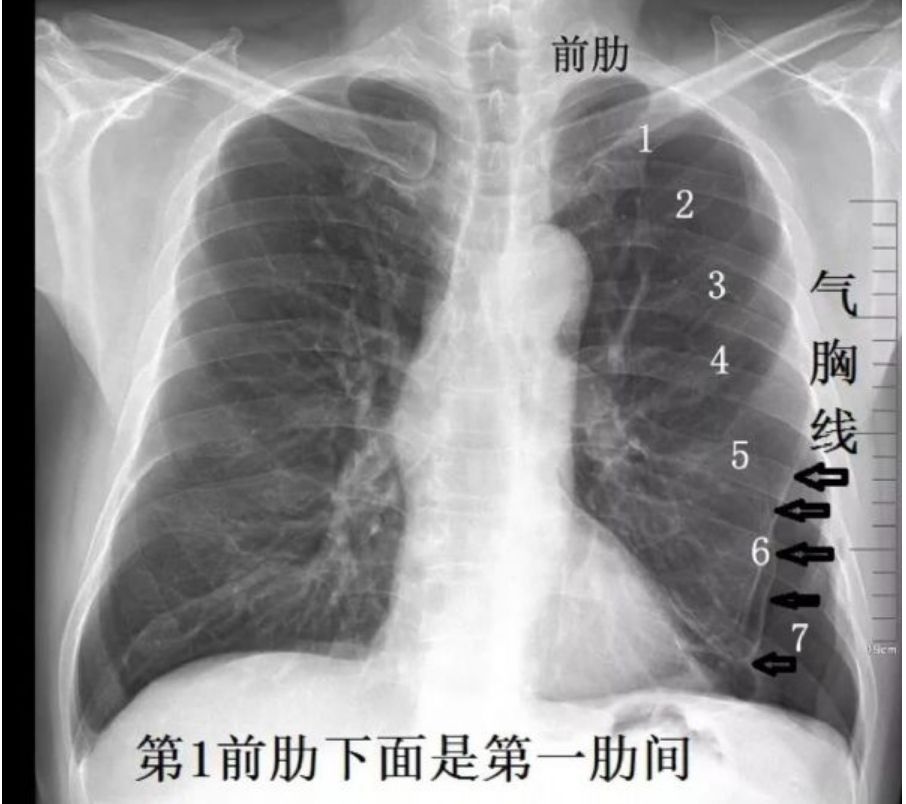

气胸的x线影像描述

气胸的x线影像描述,气胸x线胸片典型表现

气胸x线胸片典型表现

典型气胸x线胸片图解

气胸x线胸片图解

气胸胸片典型图片

气胸的x线表现

气胸x线胸片表现

气胸x线胸片描述

气胸x线胸片

气胸X线

气胸胸片